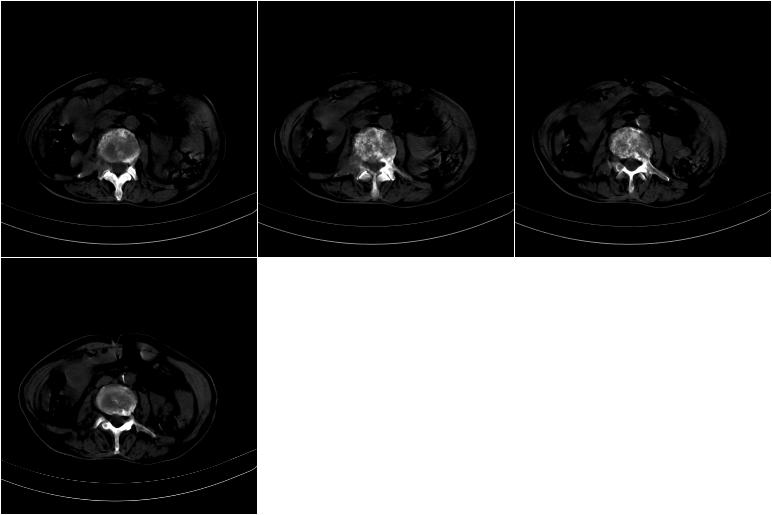

以下是引用奥特之父在2009-4-20 19:58:00的发言:[br]支持胰腺癌并转移性病变。